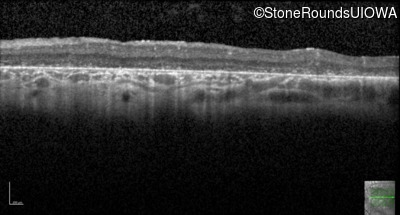

Age at visit: 6 years

OD OS

Age at visit: 5 years

Age at visit: 7 years

Age at visit: 8 years

Age at visit: 9 years

Age at visit: 11 years

Age at visit: 12 years

Age at visit: 13 years

Age at visit: 14 years

Age at visit: 17 years